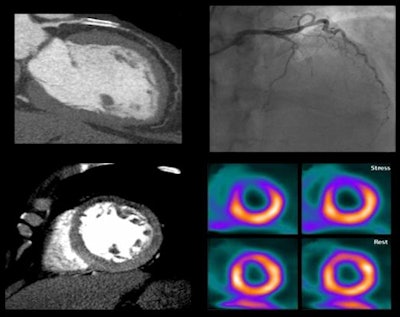

Image of CORE320 patient shows an occluded left anterior descending (LAD) stent on CT and catheterization, with the corresponding anterior wall defect demonstrated by CT perfusion and SPECT. Image courtesy of CORE320 investigators.The value of CT perfusion

Both invasive coronary angiography and CTA provide morphologic data, but they lack the physiologic information needed to determine the hemodynamic significance of a lesion. Proving that functional significance requires either catheter-based fractional flow reserve techniques, or noninvasive modalities such as SPECT myocardial perfusion imaging (MPI), PET, or MRI, the authors explained (Eur Heart J, November 19, 2013).